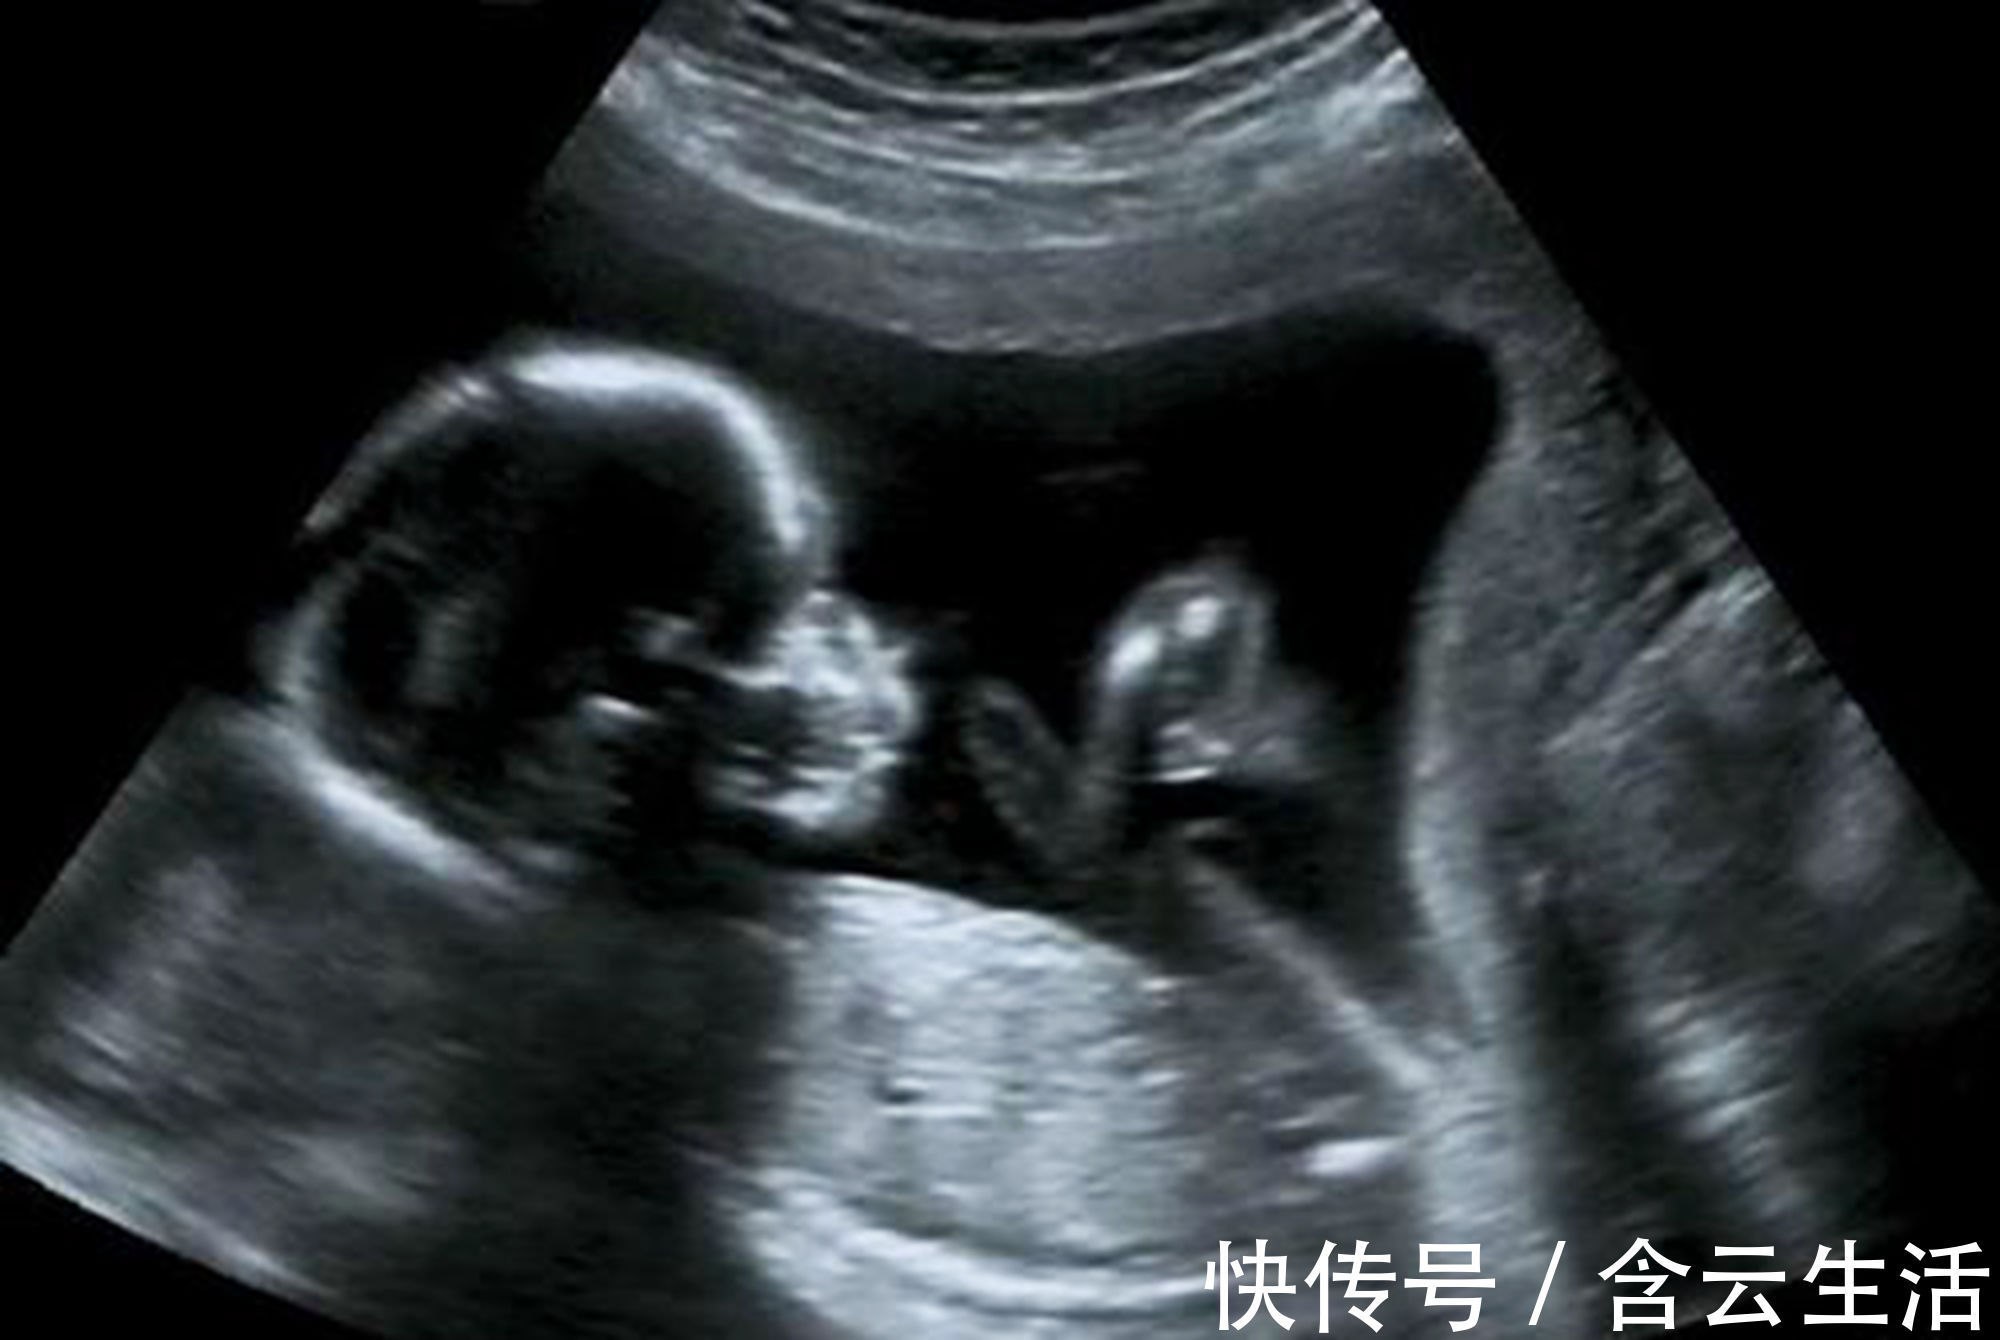

孕早期B超单上的四个指标,暗含了胎儿的“小秘密”,你看得懂吗?孕囊,卵黄体,胎心,胎芽,被誉为判断胎儿的“四大指标”,孕早期这些数据,有着极其重要的临床意义。

在B超的图像中,孕囊仿佛一个黑色的小球,周围包裹着白色的外边。孕囊的变化很神奇,在孕妈妈怀孕5周时,医生就可以通过B超观察到它的影响了,随着胎宝宝的不断成长,到怀孕11周左右时,原始的孕囊却完全消失不见了,转换为胎盘,继续为胎儿提供营养。